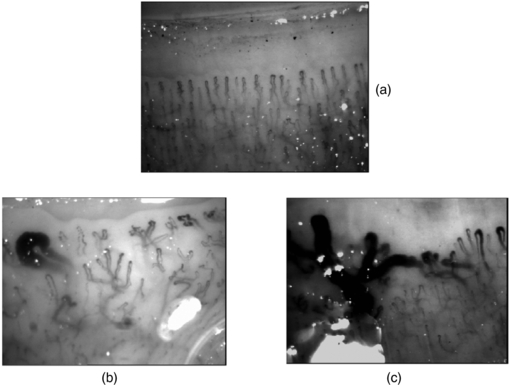

More than 10% of patients who attend a specialist centre with RP will eventually develop a scleroderma-spectrum connective tissue disease (Spencer-Green 1998). Along with the presence of specific autoantibodies, an abnormal NFC is a key risk-factor for the development of SSc in patients presenting with RP. SSc is a multi-organ disease characterized by tissue fibrosis and immune/microvascular abnormalities. The disease is very important to diagnose early so that it can be treated aggressively at an early stage (Cutolo et al 2008, 2010) (figure 15).

Figure 15. Example wide field capillaroscopy images from (a) a healthy subject and (b) and (c) significant microangiopathy in systemic sclerosis (SSc) with giant capillary structures and architectural disorganization clearly seen.

Standard image High-resolution imageThe presence of giant capillaries and micro-haemorrhages on NFC is sufficient to identify the 'early' scleroderma pattern, and an increase in these features along with the progressive loss of capillaries (active pattern) is followed by neo-angiogenesis, fibrosis and 'desertification' (late pattern) (Cutolo et al 2013). The sensitivity of the American College of Rheumatology's classification criteria for SSc increases from 67% to 99% with the addition of these specific NFC abnormalities. Telangiectasiae may form on the face and hands along with digital ulcers. Based on the appearance of the scleroderma pattern on NFC, almost 15% of patients progress from primary to secondary RP over a mean follow-up period of 29 ±10 months. Follow-up by NFC (every six months) is suggested for RP patients. A scoring system for NFC changes is available, and scores change significantly during follow-up of SSc patients (Cutolo et al 2013).